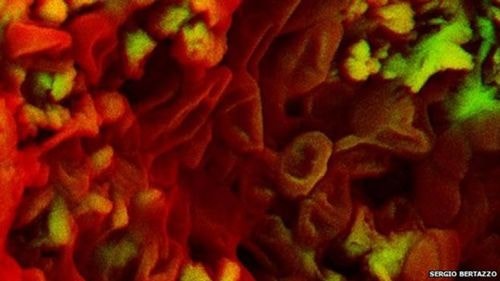

Phát hiện phương pháp 'vô hiệu hóa' sự lan rộng tế bào ung thư

Các nhà khoa học tại Viện nghiên cứu y khoa Garvan, Australia, vừa tìm ra phương pháp có thể ngăn chặn sự lan rộng của tế bào ung thư, đem lại hi vọng cứu sống hàng nghìn người mỗi...